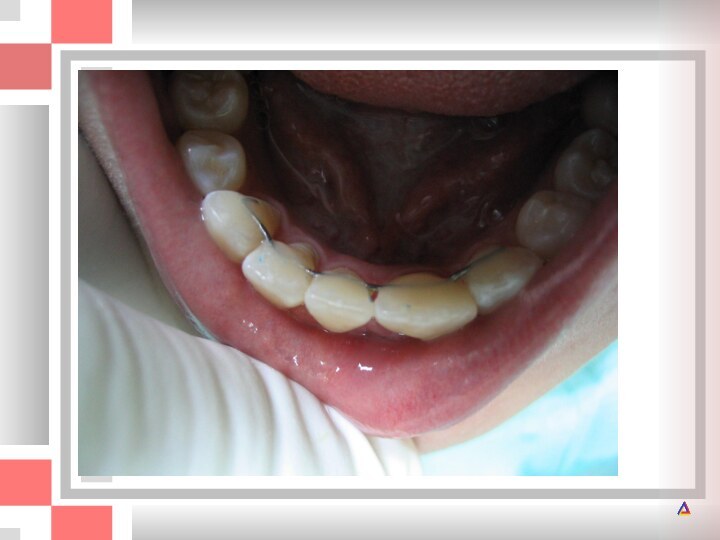

А - перелом коронки верхнего левого центрального резца по II классу;

по II классу; Б - через 7,5 лет после реставрации.

Приемлемый функциональный и эстетический результат, хотя при внимательном осмотре можно обнаружить стирание режущего края пломбы.